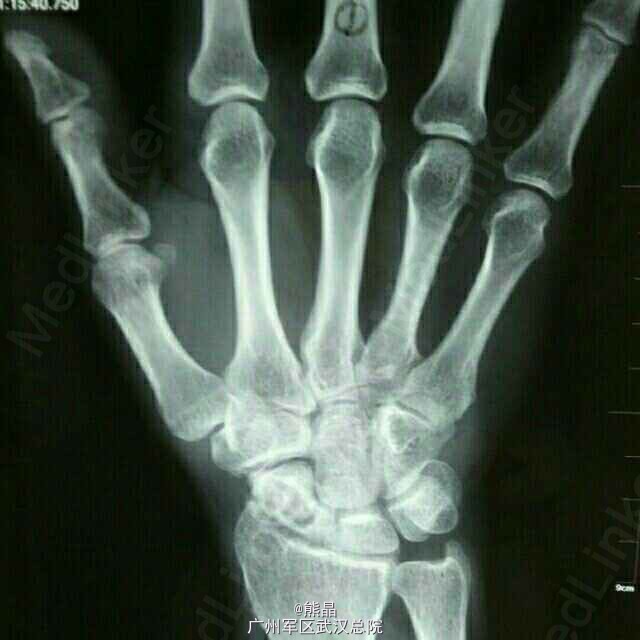

腕关节结核三例

熊医师   中国人民解放军中部战区总医院

腕关节结核在上肢关节中居第三位。病灶多开始于骨骼,或同时累及滑膜,单纯为滑膜型者少见。 病理上干酪型多于肉芽型。多见于青少年,10岁以下较少发病,病灶较易侵犯腱鞘而影响手的功能。脓肿易穿破皮外形成窦道。 X线表现,早期单纯滑膜结核,可见骨质疏松和软组织肿胀。尺桡骨下端结核可有死骨中心型和溶骨性破坏的边缘型。晚期可见多个腕骨尺,桡下端和掌骨关节面广泛破坏。腕关节出现畸形。